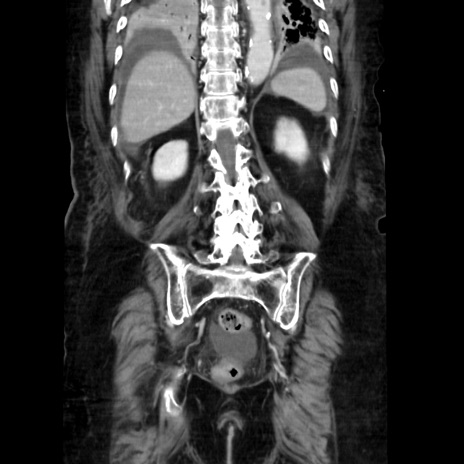

症例40(冠状断像)

冠状断像